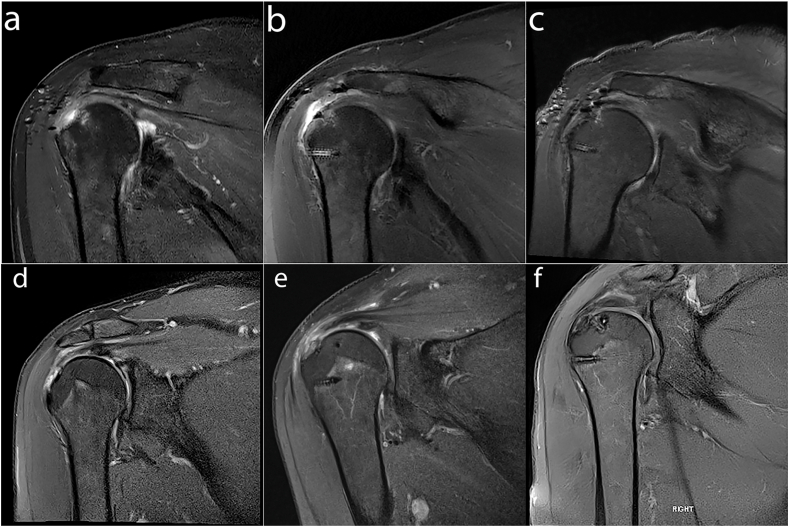

MRI assessment of 17 patients at 12 months revealed complete healing in 64.8% patients (11/17), 3 partial thickness re-tears (17.6%) and 3 full thickness re-tears (17.6%). Representative baseline T2w fat suppressed MRI images (Fig. 7a and c) from patients proceeding to either mini open (Fig. 7e) or arthroscopic (Fig. 7f) surgical procedures, show full thickness supraspinatus detachment from the RC anatomical footprint prior to repair. At 6 months following surgical repair there is evidence of BCS path signal and there is no longer a fluid filled defect at the footprint (Fig. 7b and e) in comparison to baseline, with the repaired tendon containing mildly increased signal intensity. MRI imaging at 12 months (Fig. 7c and f) indicates successful healing of the full thickness supraspinatus tendon tears.

Fig. 7.

T1-weighted coronal magnetic resonance images from patients at baseline (a & d), 6-months (b & e) and 12 months (c & f) following either mini-open (a–c) or arthroscopic repair (d–f) of the RC with a BCS. (a) Supraspinatus full thickness tear extending to infraspinatus with associated tendinopathy. (b) Supraspinatus tendon displayed intermediate signal intensity of BCS patch. No fluid filled defect at the footprint was seen. (c) Supraspinatus tendon repair intact with no evidence of re-tear. (d) Supraspinatus full thickness tear extends to the footprint. (e) The region of supraspinatus and infraspinatus tendons display intermediate signal intensity, reflecting the repair process of BCS. (f) Supraspinatus full thickness tear resolved with no evidence of re-tear.